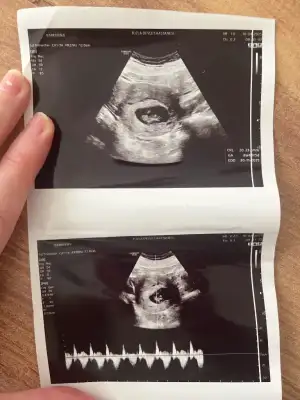

Ay çok merak ediyorum bizede bakar mısınız karından ultrason ile bakıldı görsellerde ilk görsel 10+4 diğer görseller 6+4 haftalıkken bir oğlum var bide kızımız olur inşallah :)Kızlar 6-8 haftalık ultrason görüntülerinizi atın tahmin yapalım . Ya da cinsiyeti öğrenen annelerimiz 6-8 haftalık görüntülerini atsın bize de fikir olsun

Yok karindan ultrasonBir oğlum var kızım olmasını da isterimsizinde Vajinal ultrason görüntüsümüydü

Umarım kızınız olur ama bence bebeğiniz erkekAy çok merak ediyorum bizede bakar mısınız karından ultrason ile bakıldı görsellerde ilk görsel 10+4 diğer görseller 6+4 haftalıkken bir oğlum var bide kızımız olur inşallah :)